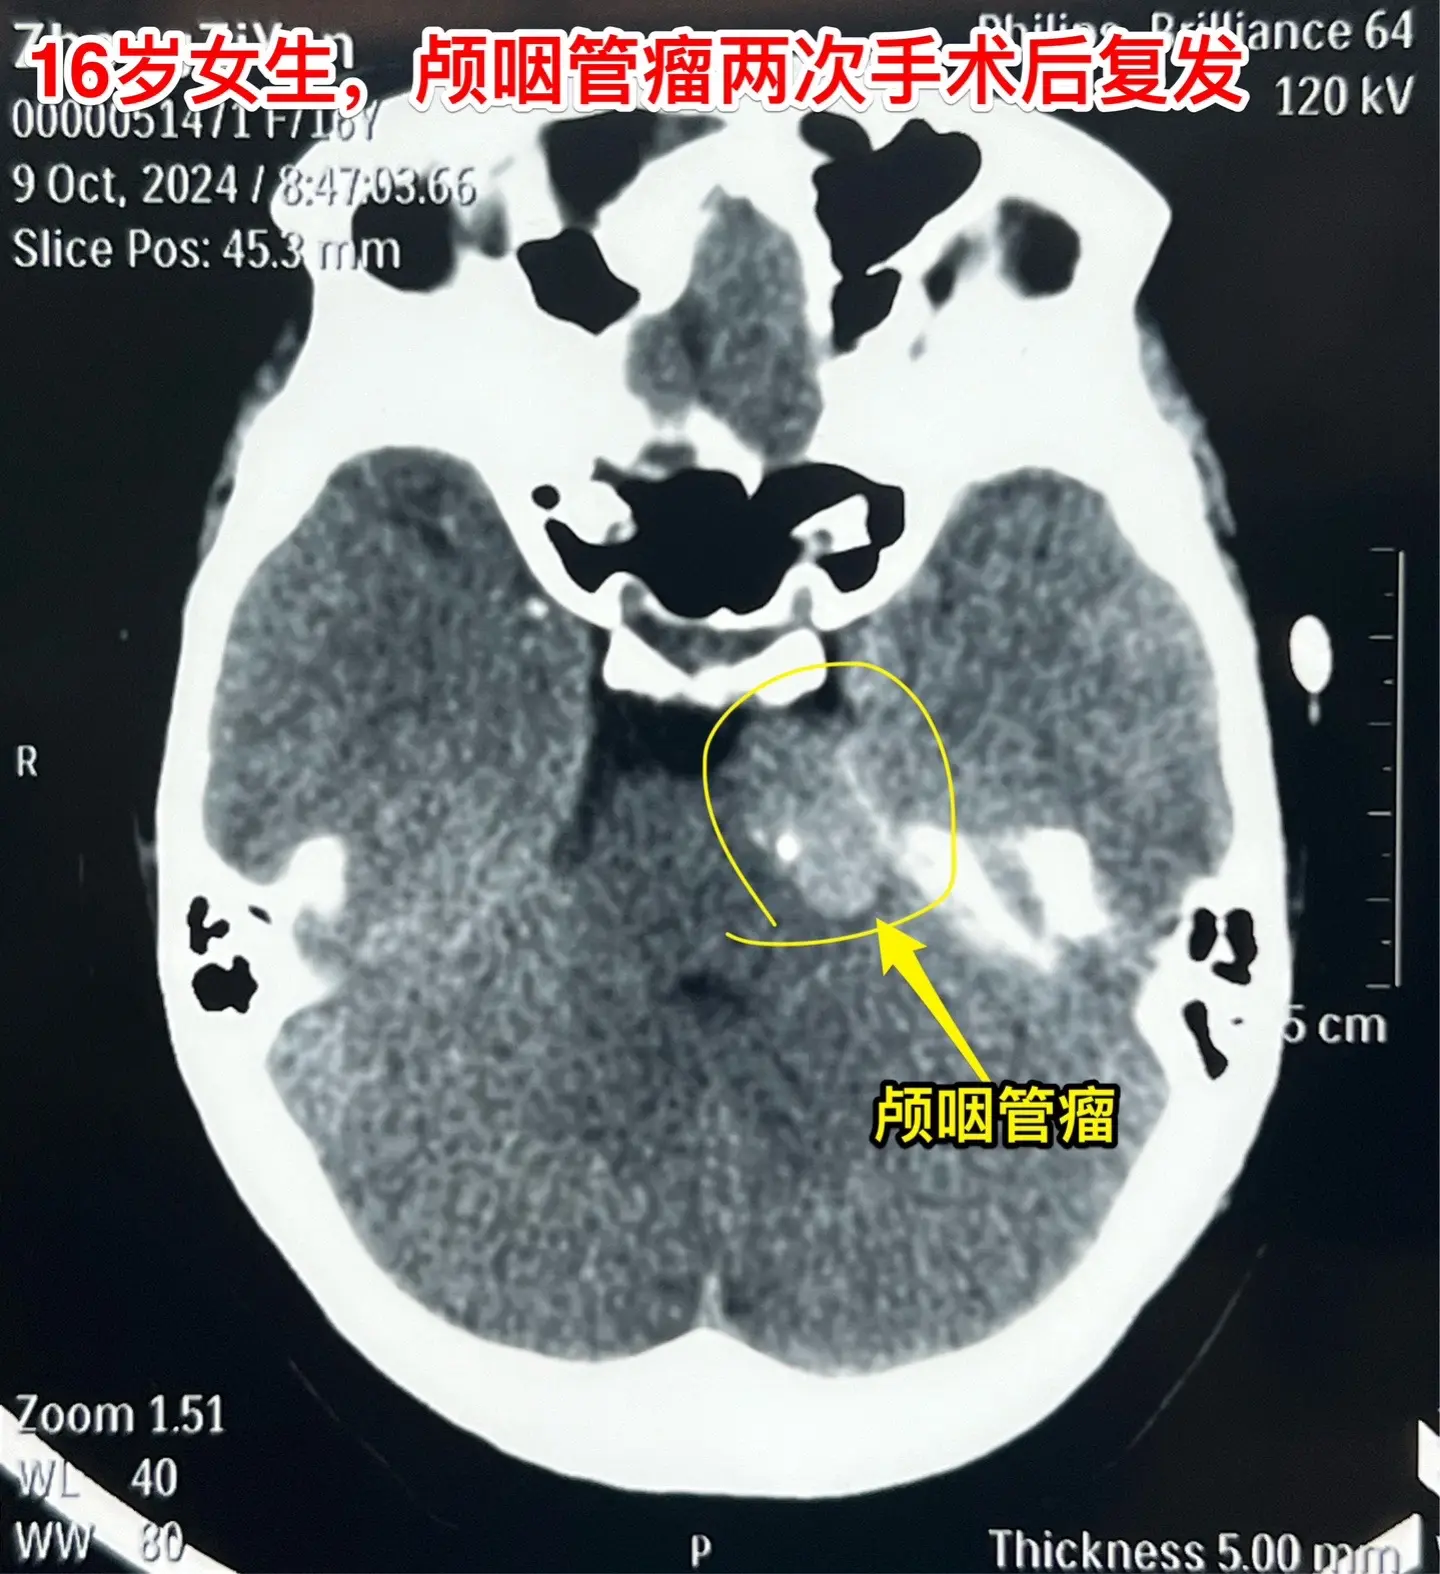

3次复发的颅咽管瘤也要积极治疗。16岁杭州女生,因颅咽管瘤于10年前在外院行开颅手术。8年前发现颅咽管瘤复发(在右侧额叶-鞍区)在我科作了手术,随后多年复查磁共振,7年内均未见肿瘤复发。本以为她的颅咽管瘤已经得到治愈,不曾想八个月前行磁共振检查发现肿瘤有复发迹象,体积很小,观察八个月常规复查磁共振发现肿瘤体积增大了许多,见图,肿瘤起源于左侧桥脑-中脑表面,和普通的颅咽管瘤位置不同。 10月11日作了手术,将这个复发肿瘤彻底切除了。手术后女孩子恢复很顺利,希望经过三次手术后肿瘤不再复发。